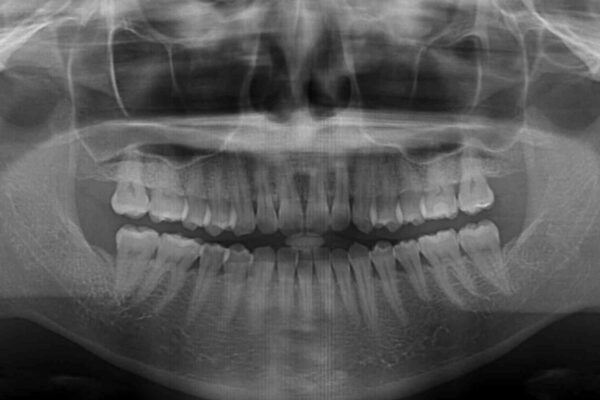

上顎前歯が捻れて前方に飛び出しており、下顎前歯もそれに沿うようにデコボコとなっていました。

IPR(歯と歯の間を削る処置)によりスペースを獲得して上下顎前歯のデコボコを改善し、飛び出している前歯が引っ込むように設定し、インビザラインにて矯正治療を行うこととしました。

• 【モニター】前歯のデコボコをインビザラインで改善 治療前画像